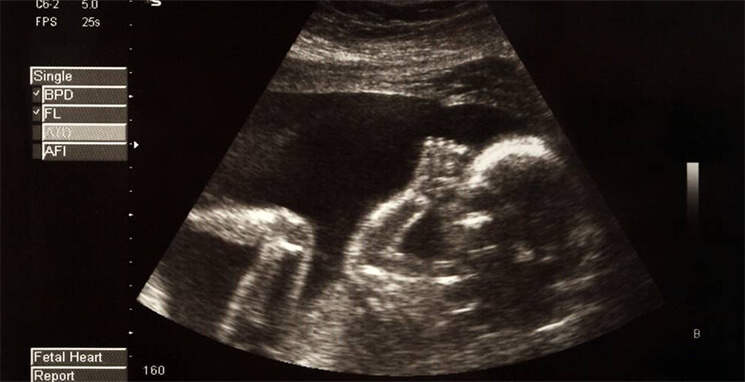

ultrasound

A screening test is available for pregnant women between 10 and 14 weeks of pregnancy. It is known as a combined test because it combines an ultrasound scan with a blood test for a proper diagnosis.

This scan determines “nuchal translucency” by measuring the fluid at the back of the baby’s neck. The doctor checks your age and the test results to assess the chances of the baby having Edwards’ syndrome.

However, obtaining a nuchal translucency measurement depends on the baby’s position in the uterus and may not always be possible.

If the mother is too far into the pregnancy, the doctor may offer to do a mid-pregnancy scan. It is a test done at 20 weeks of pregnancy. Its main motive is to test for Edwards’ syndrome symptoms in the baby that point towards the physical disorder.

One or more of these abnormalities are observed in the ultrasound findings in 90 per cent of the cases: